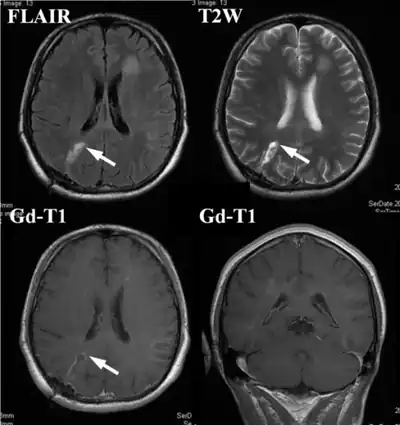

| An example of a ring-enhancement around a lesion in gliobastoma. In tumefactive multiple sclerosis, the ring-enhancement is open, not forming a complete ring. | |

MRI diagnosis is based on lesions that are disseminated in time and space, meaning that there are multiple episodes and consisting of more than one area.[39] There are two kinds of MRI used in the diagnosis of tumefactive MS, T1-weighted imaging and T2-weighted imaging. Using T1-weighted imaging, the lesions are displayed with low signal intensity, meaning that the lesions appear darker than the rest of the brain. Using T2-weighted imaging, the lesions appear with high signal intensity, meaning that the lesions appear white and brighter than the rest of the brain. When T1-weighted imaging is contrast-enhanced through the addition of gadolinium, the open ring enhancement can be viewed as a white ring around the lesion.[40] A more specific MRI, Fluid attenuation inversion recovery (FLAIR) MRI show the signal intensity of the brain. Subjects with tumefactive multiple sclerosis may see a reduction of diffusion of the white matter in the affected area of the brain.[11]